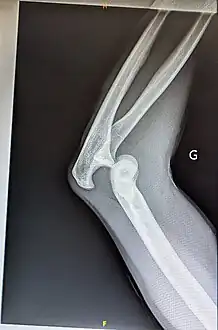

Prognosis varies depending on the location and extent of the dislocation. The prognosis of a shoulder dislocation is dependent on various factors including age, strength, connective tissue health and severity of the injury causing the dislocation.[23] There is a good prognosis in simple elbow dislocations in younger people. Older people report more pain and stiffness on average.[23] Wrist dislocations are often difficult to manage due to the difficulty in healing the small bones in the wrist.[23] Finger displacement towards the back of the hand is often irreducible due to associated injuries, while finger displacement towards the palm of the hand is more readily reducible.[23] Overall, recovering from a joint dislocation can range from a few weeks to months, depending on the severity of the injury.[4]